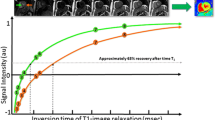

Magnetic resonance of protons varies between tissues, depending on the macromolecular environment that water finds itself in. The T1 relaxation time (longitudinal relaxation time, measured in milliseconds) is a tissue-specific magnetic property and is determined by how rapidly protons re-equilibrate their spins within their environment after been excited by radiofrequency pulse. T1 varies with measurement technique and MRI field strength. Regional difference in T1 can be visualized by T1-weighted sequences following an intravenous bolus of extracellular contrast, gadolinium, to evaluate myocardial scar or focal fibrosis.

Gadolinium is an extracellular agent not able to enter through intact cell membrane and cleared from the blood pool after minutes. In tissue with damaged or dead cells, these kinetic effects are delayed and there is a higher accumulation of contrast due to ruptured cell membranes allowing gadolinium to passively diffuse into the cellular compartment. Gadolinium changes magnetic properties by shortening T1 of a tissue. If at this point, a T1-weighted inversion recovery sequence is performed, with the inversion time (TI) set manually by the operator to null “normal” remote myocardium, this will appear black and scar tissue white [8].